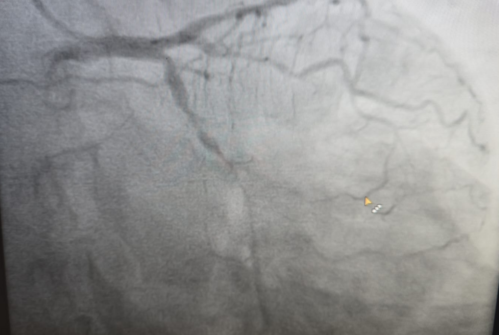

Success in Complex Left Main Bifurcation Angioplasty by Dr. Hasmukh Gujar, Cardiologist

Dr. Hasmukh Gujar, a skilled Cardiologist near Swargate on Satara Road, has achieved remarkable success with a complex left main bifurcation angioplas...